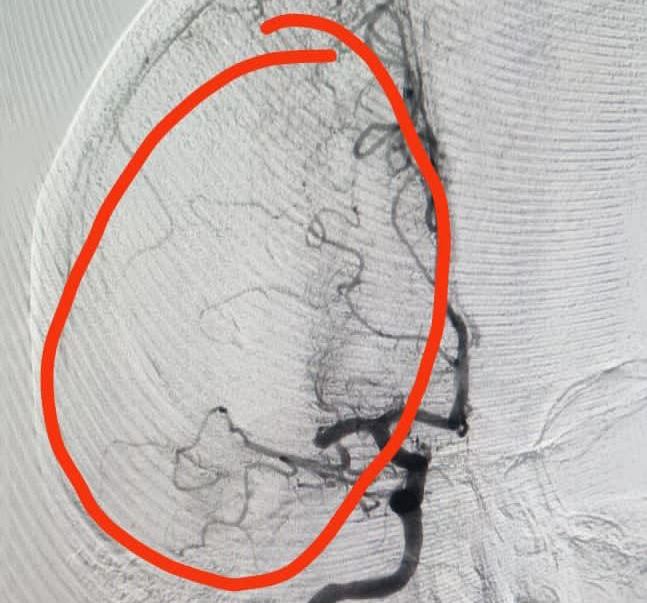

В Волгограде врачи областной клинической больницы № 1 успешно провели операцию 43-летней жительнице Санкт-Петербурга. Хирурги удалили тромб из головного мозга женщины, которая гостила у родственников в нашем городе.

На машине скорой помощи её доставили в больницу, где врачи провели обследование и нашли причину плохого самочувствия женщины. У пациентки наблюдался тромбоз средней мозговой артерии справа.

Операцию специалисты больницы провели в рентгеноперационной отделения сосудистой хирургии, которая оснащена современным оборудованием в рамках федерального проекта «Борьба с сердечно-сосудистыми заболеваниями» нацпроекта «Здравоохранение». Сейчас пациентка чувствует себя лучше и продолжает амбулаторное лечение.